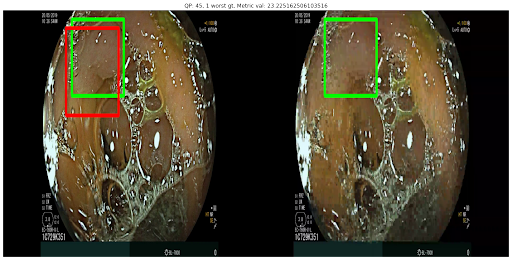

Compression quality: Figure 1 (middle) shows the compression rate versus frame quality distribution for H264 and HEVC. Importantly, we see that H264 and HEVC compress the most medically relvant frames statistically significantly worse: treating each QP value separately, a two-sided Kolmogorov-Smirnov test between distribution of PSNR-CbCr shows that the frame quality is lower for polyp frames than for all frames. For each QP value, , , H264 (HEVC) maximum p-value over all tests is (), mean test statistic (). For the same test with PSNR-Y, see the Appendix. Figure 2 top two rows show the lowest quality compressed frames inside the body according to PSNR-CbCr, with and without polyps (for the absolute worst quality compressed frames, see the Appendix).

A.3 Lowest quality compressed frames